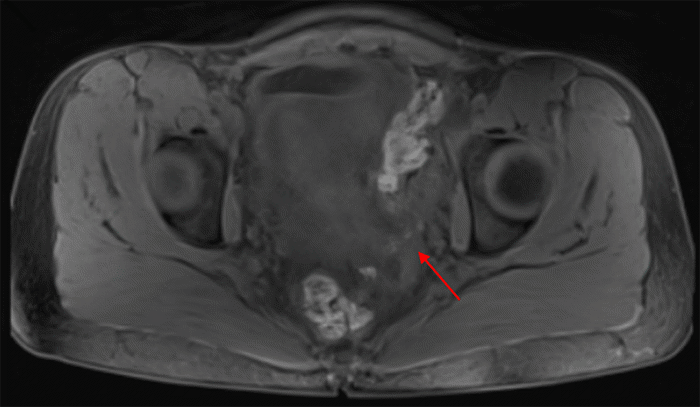

Several months prior to presentation, she experienced early satiety, abdominal bloating, and constipation, prompting medical evaluation. An abdominal ultrasound revealed a concerning 22 × 22 × 16 cm cystic structure abutting the uterine fundus. A follow-up pelvic MRI confirmed a large midline abdominal cystic lesion (Figure 1) but noted normal ovaries and a uterus separate from the mass. The lesion abutted the right ovary and uterus but did not appear to arise from them. Hyperintense foci, concerning for possible peritoneal seeding, were also identified (Figure 2).

Figure 1. MRI Pelvis with Large Intraabdominal Mass. Published with Permission

Figure 2. T1-Weighted MRI Pelvis Reveals Multiple Hyperintense Foci Suggestive of Peritoneal Seeding. Published with Permission